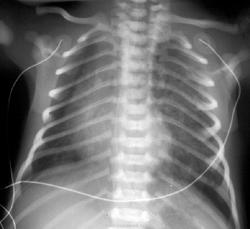

Врожденная долевая эмфизема

Этот порок развития характеризуется растяжением части легкого (чаще одной доли). Для его обозначения употребляют термины "врожденная долевая эмфизема", "локализованная эмфизема", "обструктивная эмфизема", "гипертрофическая эмфизема". Наиболее часто поражение затрагивает верхнюю или среднюю долю. Врожденная долевая эмфизема нижней доли легких встречается крайне редко. Впервые клиническую картину заболевания описал Robertson и James в 1951 году. Истинные причины порока остаются невыясненными. Однако некоторые авторы связывают его возникновение с аплазией хрящевых элементов бронхов, гипоплазией эластических волокон, гипоплазией гладких мышц терминальных и респираторных бронхиол и другими нарушениями в структурных единицах легочной ткани. Эти факторы создают предпосылки для возникновения клапанного механизма, способствующего чрезмерному вздутию соответствующей части легкого и развитию дыхательных нарушений. Врожденная долевая эмфизема встречается примерно у одного ребенка на 100 000 родившихся.

Клинические проявления обусловлены наличием и выраженностью симптомов дыхательной и сердечно-сосудистой недостаточности. В патогенезе дыхательной недостаточности играют роль следующие факторы: выключение из дыхательной функции большого объема легочной ткани (отсутствие дыхательной функции в порочно развитом отделе легкого и коллабирование нормально сформированных отделов в результате сдавления их чрезмерно растянутыми отделами порочного легкого), а также значительным процентом шунтирования крови в коллабированной части легкого.

Повышение внутригрудного давления и смещение средостения, нередко встречающиеся при этом пороке развития, являются другим патогенетическим механизмом, обусловливающим сердечно-сосудистые нарушения у таких больных.

При декомпенсированной форме порок проявляет себя с рождения. С первых дней жизни отмечаются общий цианоз, одышка, дыхательная асимметрия (отставание в акте дыхания вздутой половины грудной клетки), беспокойство ребенка, частый сухой кашель, приступы асфиксии при кормлении. Могут отмечаться потери сознания и гипоксические судороги. В недиагностированных случаях один из асфиксических приступов может привести к остановке сердца и летальному исходу. При отсутствии хирургического лечения больные редко живут более 2-3 месяцев.